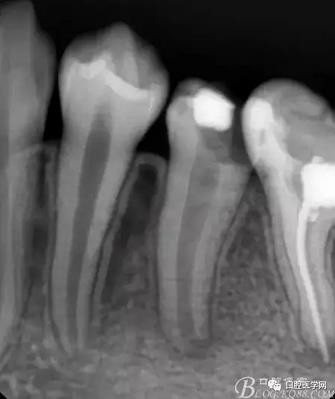

X檢查:

36根管治療遺漏根管,欠填以及超填,根尖有陰影 ,有繼發(fā)齲;35根尖部有陰影,未行根管治療,有繼發(fā)齲已穿髓

診斷:35,36為慢性根尖炎